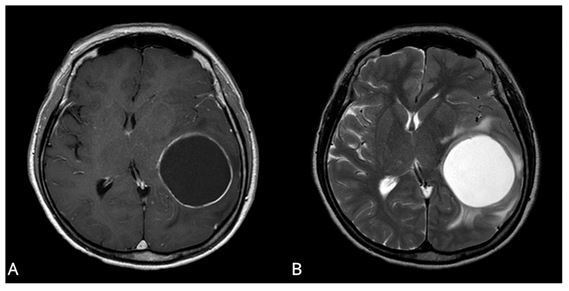

교모세포종 환자의 MRI 사진. 체액(fluid) 성분이 대부분인 낭종 (cyst)이 있는 낭성군(A)환자가 비낭성군(B) 환자에 비해 유의하게 생존기간이 길었다.

성향 점수 매칭 (propensity score matching) 통계를 활용해 두 군의 다른 예후인자와 연관된 인자를 동일하게 맞춘 후, 카플란-마이어 생존 곡선을 분석한 결과, 낭성군의 생존기간이 28.6개월로 비낭성군의 18.8개월 보다 유의하게 길었다.

다변량 분석에서도 낭이 종양에서 차지하는 비율이 높을수록 환자의 생존기간이 유의하게 길었다.